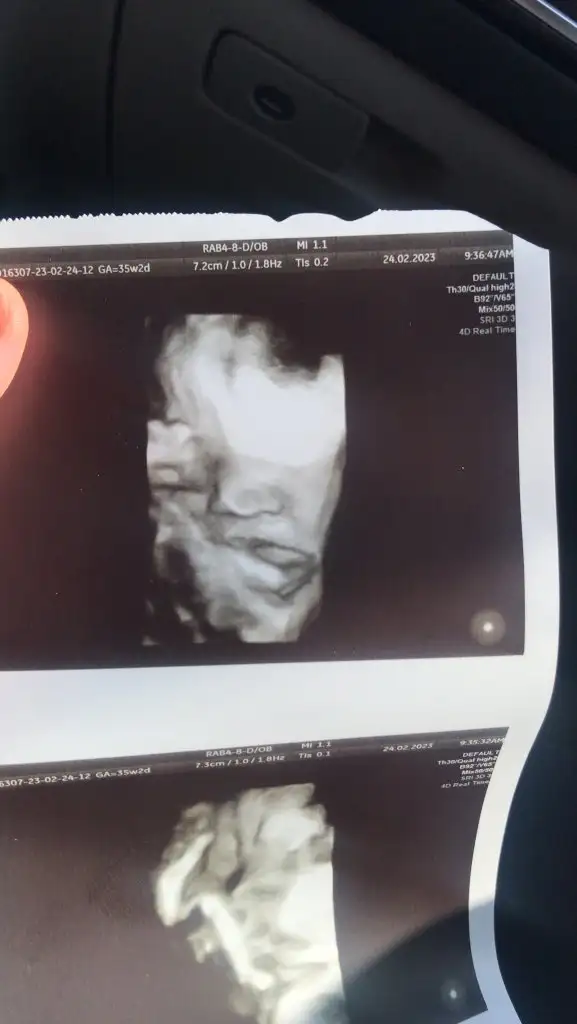

Maşallah kuzucuğaaTeyzeleri alin’den size selam getirdim35+2 2700 gram her şey yolunda. Böyle giderse 39 haftayı bekleriz dedi bakalım hayırlısı sağlıklısı nasilsa öyle olsun plasentam eskimiş sanırım gebeliğin son zamanlarında oluyormus böyle onu takip edecek,su iyiyse sıkıntı yokmuş su an icin su iyi. Haberler böyle

23 Mart direnisimiz devam ediyor yaniMaşallah kuzucuğaaaynıyız canım bende şimdi çıktım doktordan 35+3 banada 39 u bekleriz 20 martı görelim dedi

Maşallah kuzuya nasıl da yemelik duruyorTeyzeleri alin’den size selam getirdim35+2 2700 gram her şey yolunda. Böyle giderse 39 haftayı bekleriz dedi bakalım hayırlısı sağlıklısı nasilsa öyle olsun plasentam eskimiş sanırım gebeliğin son zamanlarında oluyormus böyle onu takip edecek,su iyiyse sıkıntı yokmuş su an icin su iyi. Haberler böyle